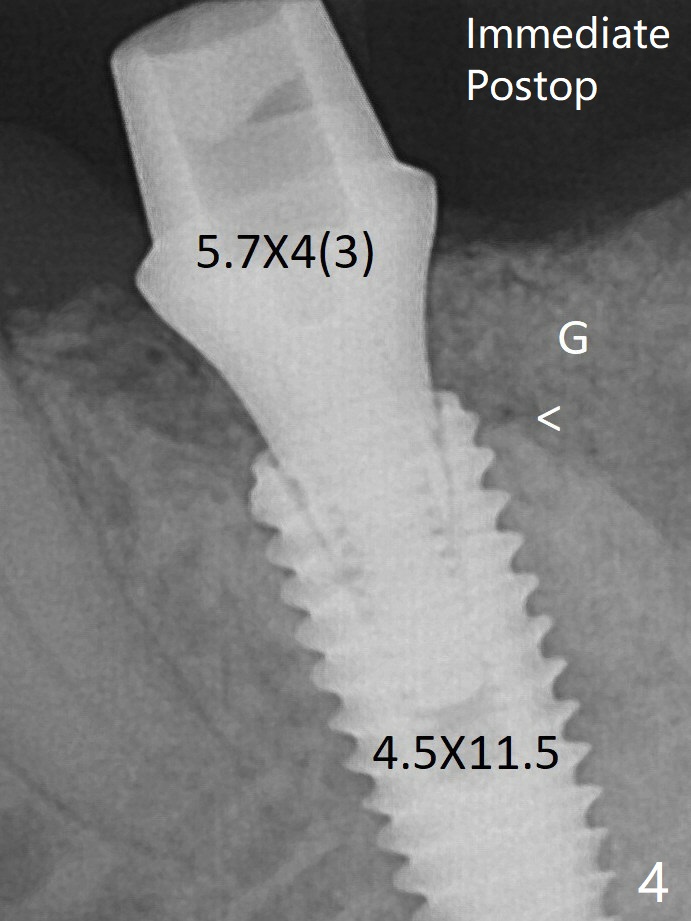

With all of measures taken (including periodontal dressing), the distal bone graft (Fig.8 *) is ~ 2 mm coronal to the crestal bone (red arrow) 6 months postop.  G: graft; <: septal crest.  In fact the abutment is incompletely seated.  The temporary crown is perforated.  The gingival cuff is erythematous.  A 6.8x5 mm healing abutment is installed.   When the patient returns for impression, take BW to determine whether the healing abutment contacts the crestal bone.